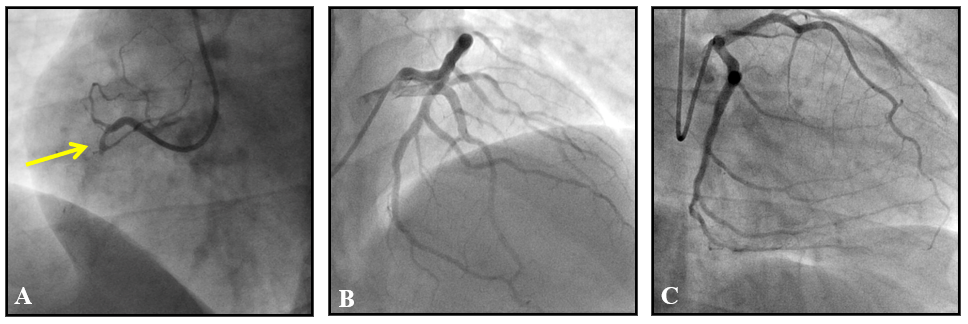

Figure 2 (A) Right coronariography in left oblique projection demonstrating occlusion of right marginal branch in proximal segment (arrow); (B) left coronary angiography in caudal projection; C: left coronary angiography in cranial projection; both showing no significant obstructive lesions in the other coronary arteries.